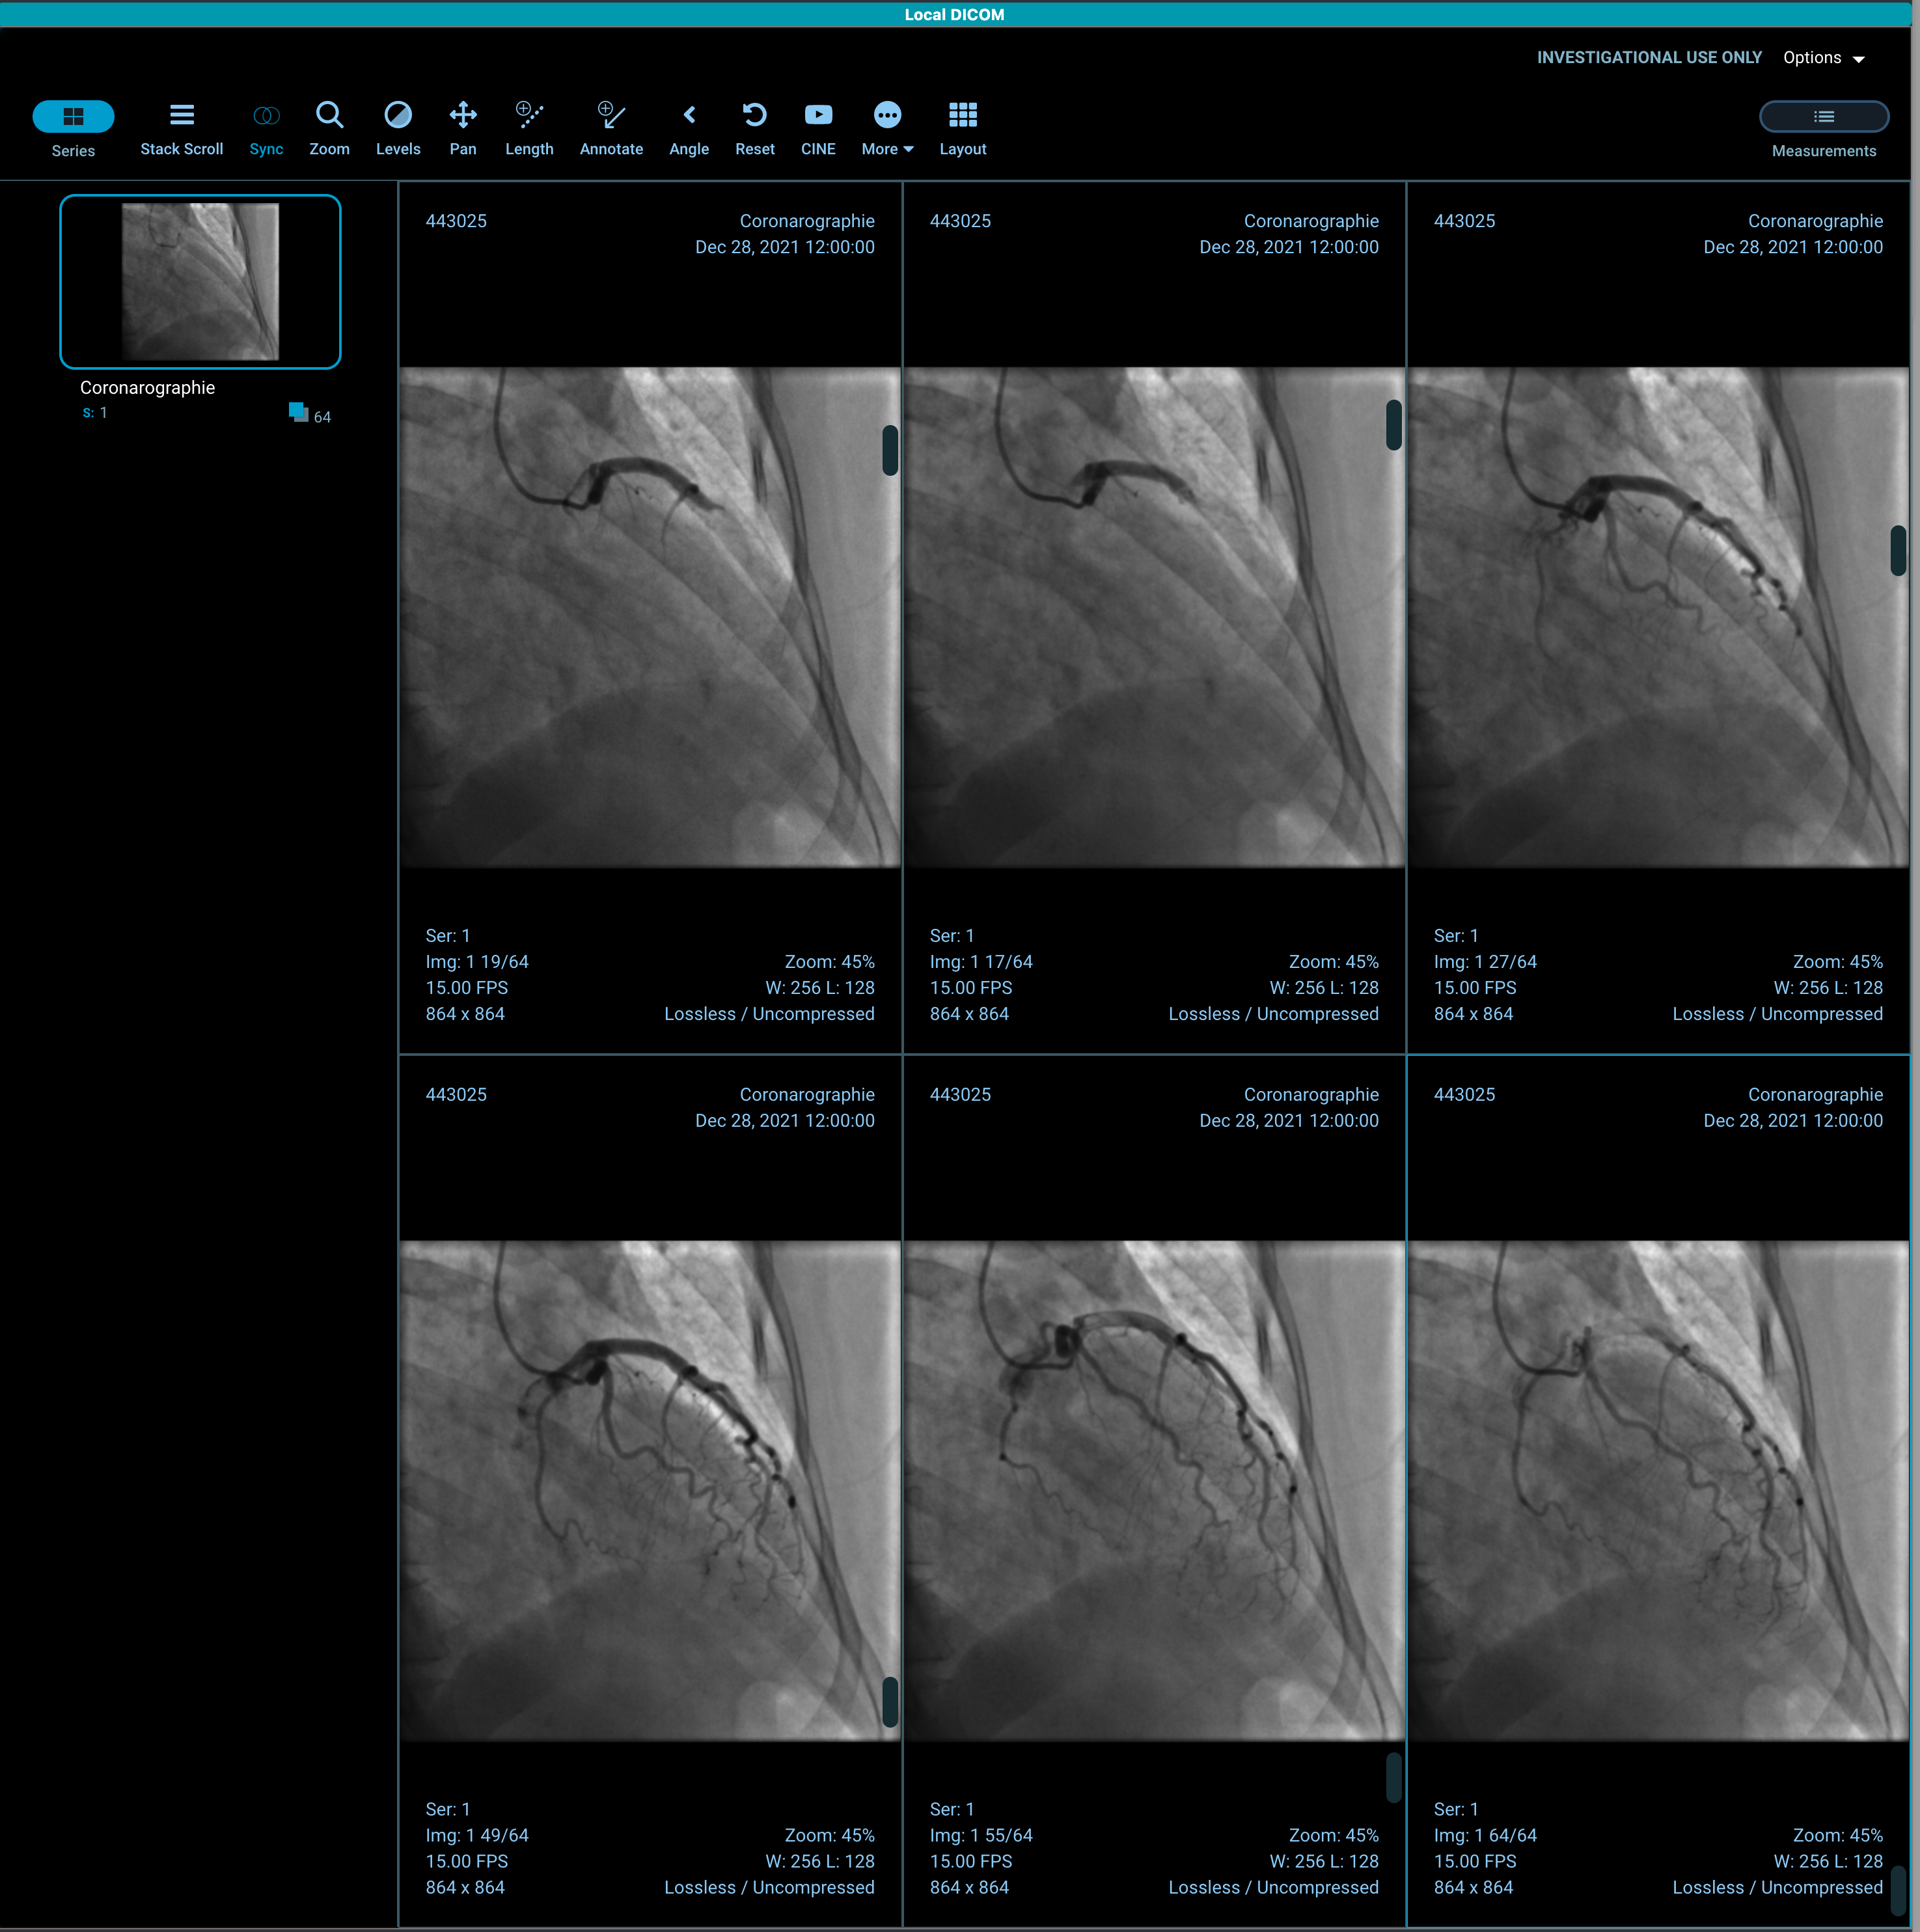

Can't load multiframe XA

Describe the Bug

Impossible to use the viewer with XA (Coro) studies.

- Use the cine play button or scroll: the image count change, the image displayed stay the first one.

Hi @jensen0914 , thanks again for your input. i can also see it but i only see 1 frame. With this version you can play the entire sequence? On my side playing or scrolling to display the next frame is not working.

In the v3 demo, I can only see the first frame even when scrolling. In my v2 build, I can see all of the frames when scrolling or using cine: